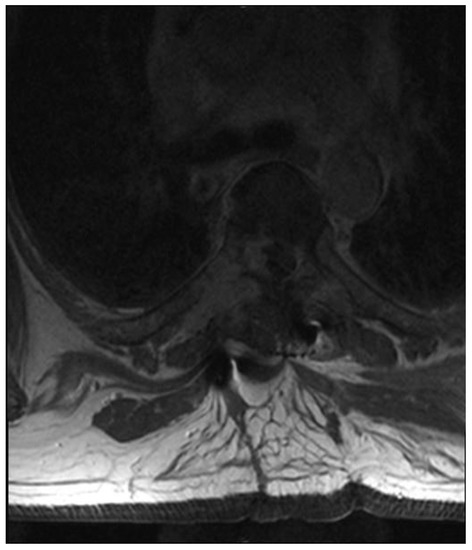

Fully Endoscopic Spine Separation Surgery in Metastatic Disease—Case Series, Technical Notes, and Preliminary Findings